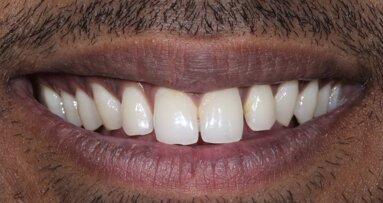

22 yr old Male walked into our dental office saying that he had a fall many years ago and his front teeth were broken. There was no associated pain or symptoms and the problem was purely aesthetic. He was only seeking treatment because he needed to get married soon. He was low on confidence while smiling and required a solution within 4 weeks.

The two maxillary central incisors were fractured and non-vital with noticeable darkening of shade [ Fig 1,2 ]. They were mal-aligned buccolingually and there was a midline diastema as well . There was no tenderness on percussion. There were peri-apical lesions associated with both incisors in the radiograph.